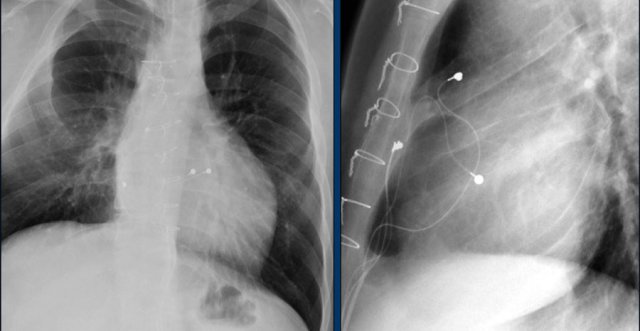

Here a biventricular pacemaker with three leads.

The right atrial pacemaker lead is located in the atrial appendage.

This lead first travels inferiorly into the right atrium and then turns upward and anteriorly where it is anchored within the trabeculae of the atrial appendage.

The left ventricular lead travels through the right atrium and the sinus coronarius and is finally positioned posteriorly into a cardiac vein on the left.